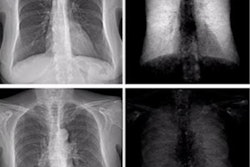

Figure 2: (A, C) Conventional attenuation-based chest x-rays and (B, D) dark-field chest x-rays in an 83-year-old man diagnosed with combined pulmonary fibrosis and emphysema (upper row) and a healthy 33-year-old man (lower row). Image courtesy of Radiology: Cardiothoracic Imaging.The patient (Fig 2: A, B) demonstrated substantially decreased dark-field signal in the upper lungs (left more than right), where emphysema is most severe, and inhomogeneous but decreased lower lung signal (due to presence of fibrosis) when compared with a healthy subject (Fig 2: C, D). The stronger manifestation of fibrosis in the right lower lobe compared with the left lower lobe, as was seen on CT images, corresponded well to the asymmetric reduction of dark-field signal in the lower fields with a right-sided predominance (Fig 2B), the authors wrote.